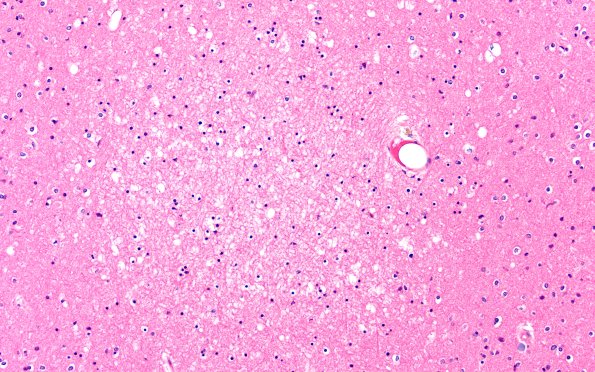

12B8 Fat Embolism (Case 12) occipital N15 20X

Cortical lesions were surprisingly numerous in the cerebral cortex of this patient. (H&E)